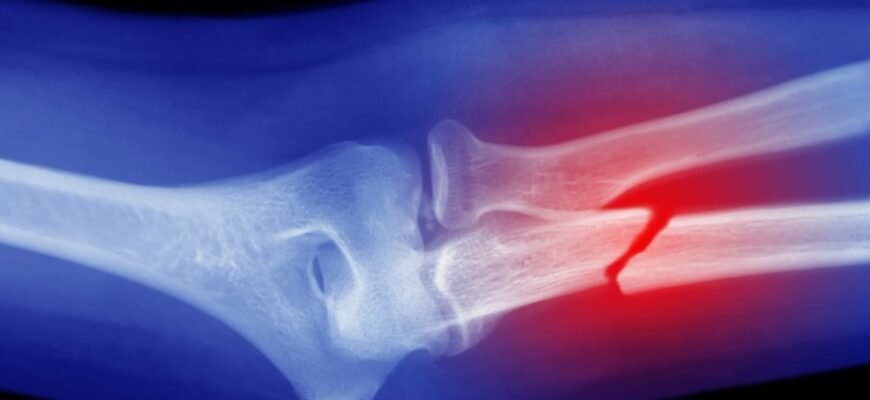

Диагностика переломов

Пойдешь к доктору — он первым делом начнет рассматривать всякие рентгены и томографии. Они круто показывают, что там внутри. Иногда видно даже больше, чем хочется. Без этого никак — знаешь ли, в гипс нужно что-то заворачивать с умом.